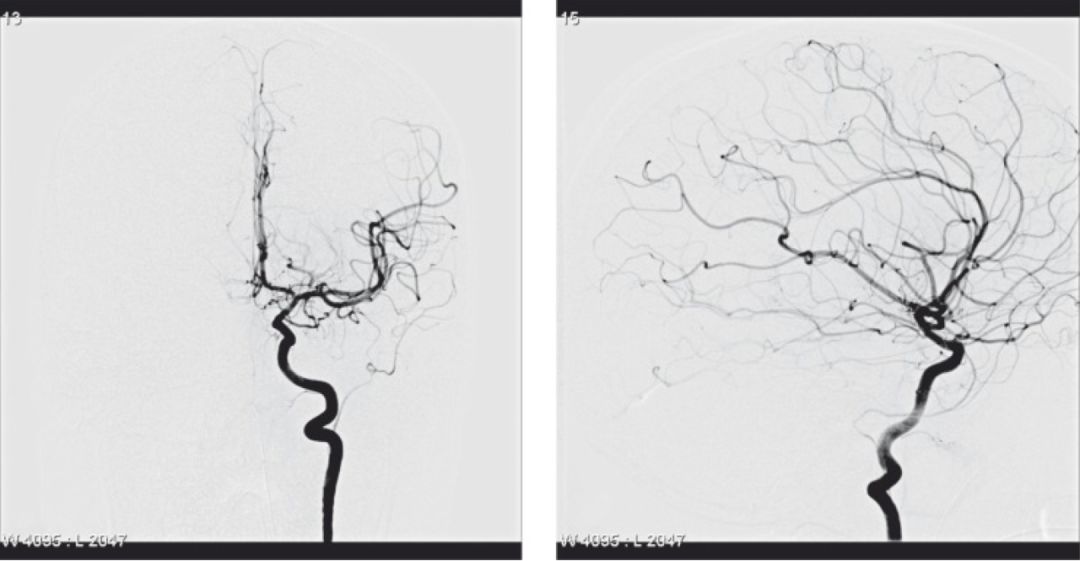

颈总动脉造影。A,侧位;B,正位。脑膜中动脉发自颈内动脉岩段(Dilenge 1980)。

原始上颌动脉来源的脑膜中动脉(Lasjaunias, 2001a)。颈内动脉的正位(A)和侧位(B)。脑膜中动脉发自颈内动脉岩段远端近破裂孔处。